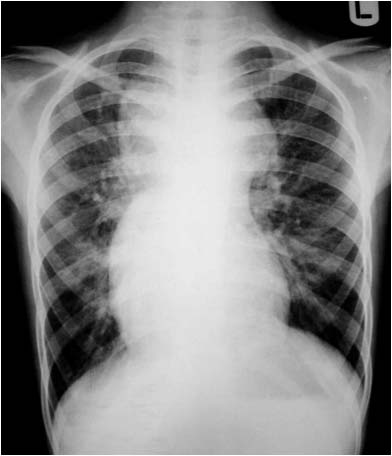

En la radiografía lateral de tórax, se ha descrito que la ausencia de la imagen del arco aórtico puede ser la clave diagnóstica de coartación aórtica. La imagen izquierda muestra el signo. Se trata del mismo paciente del Signo de las muescas costales (ver Otros signos de pleura/pared). La imagen derecha corresponde a una radiografía normal con la sombra aórtica visible (flecha).

Se han propuesto varias explicaciones para este signo; puede ser debido a hipoplasia del arco aórtico combinada con la coartación, a dilatación de las arterias braquiocefálicas (particularmente la arteria subclavia izquierda) que oscurecen el margen superior del cayado, o a hipoplasia y desplazamiento anteromedial de la porción distal del arco aórtico.